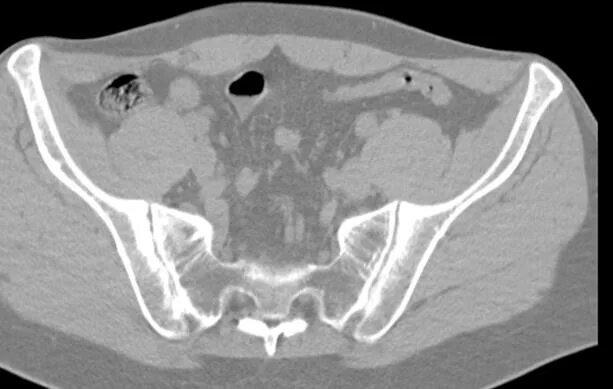

Сакроилеит на кт